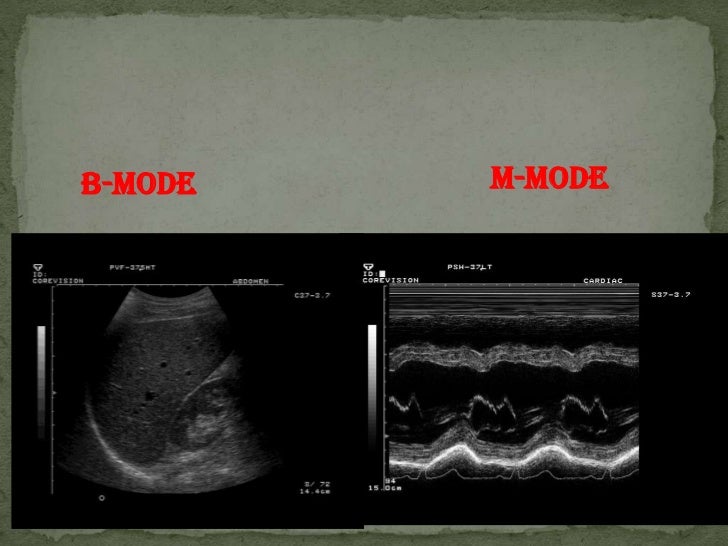

From www.slideserve.com

PPT Modes Ultrasound PowerPoint Presentation, free download ID5466126 Difference Between B Mode And M Mode Ultrasound It is represented by the conversion of ultrasound waves into. Read about the most commonly available ultrasound modes and how they are used. Modern ultrasound systems come with many controls & functions. In this guide, we’ll explore the fascinating realm of ultrasound modes and how they can enhance your imaging experience. Ultrasound modes, or options when it comes to ultrasound. Difference Between B Mode And M Mode Ultrasound.